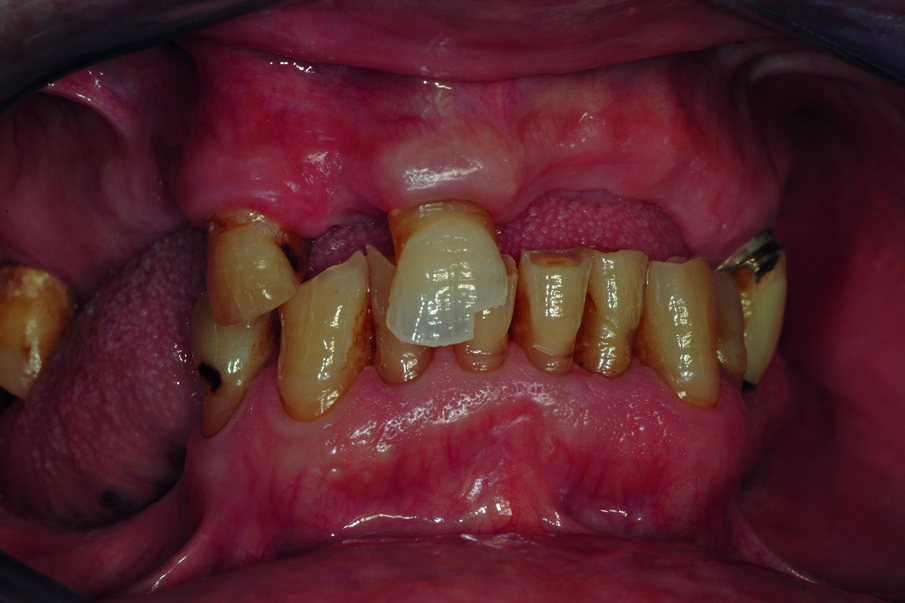

Si presenta alla nostra osservazione un paziente di anni 75, pensionato, con una richiesta di riabilitazione orale. Il paziente presenta edentulia parziale con distruzione dei tavolati occlusali e diminuzione della dimensione verticale (Fig. 1). In sede mandibolare sono conservati gli elementi dentali dal 35 al 45, mentre a livello mascellare residuano 4 elementi dentali con gravi problemi endodontici, di carie e parodontali. All’anamnesi si evidenzia la presenza di un diabete di tipo 2. Nessun problema è stato rilevato a livello ematico e pressorio.

Condividiamo con il paziente la scelta terapeutica di riabilitazione implantoprotesica che nella 1 fase consisterà in riabilitazione occlusale mediante l’applicazione di protesi provvisoria, e successivamente inserimento di 6 impianti nel mascellare a carico ritardato e seguente applicazione di barra per una overdenture. Il paziente necessita di una riabilitazione oro-implantare protesica, in quanto sia all’esame obiettivo che all’esame radiografico presenta una ridotta dimensione verticale che negli anni ha portato alla distruzione degli elementi inferiori dal 34 al 44, e persistenza di 11, 13, 17, 25 che presentano abrasioni e abfrazioni sulla superficie coronale (Fig. 2). Dopo aver condiviso con il paziente le problematiche terapeutiche dovute anche alla sua condizione di patologia sistemica, si decise, di procedere con avulsione dei denti dell’arcata superiore e contestuale inserzione di 6 impianti, per un una riabilitazione implantoprotesica overdenture su barra, a carico ritardato a 6 mesi.